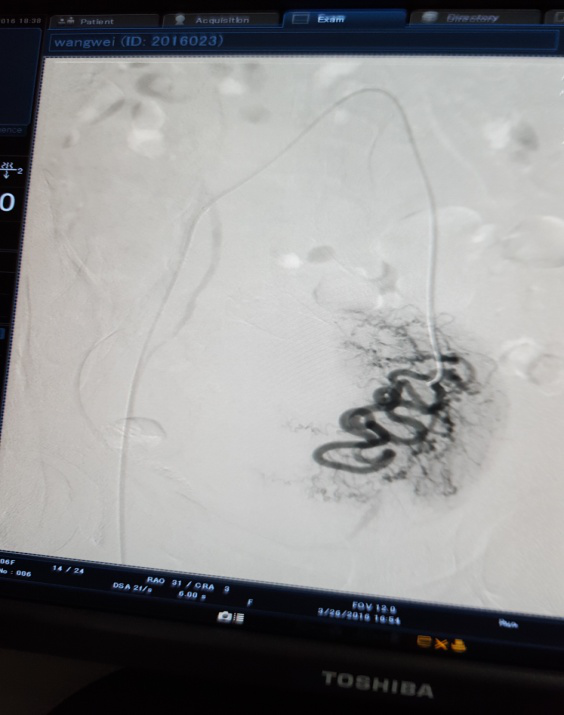

治疗前 左侧                              治疗后左侧分支血管消失

3月28日下午3点,在医院新导管室内,放射介入科主任张敏荣与任长德、李可峰医师成功地完成了新导管室建成后首例子宫腺肌症介入手术。该患者女性、40岁,因患子宫腺肌症,造成腹痛难耐,C臂下造影见:左子宫动脉增粗,分支数量增多、迂曲,用PVA颗粒栓塞迂曲的分支动脉,在妇产科保驾下,手术操作顺利。经过几天的对症治疗,各项检查指标符合出院标准,现病人已出院家中休养。该项手术的成功开展,又一次填补了市中医院该项之空白。